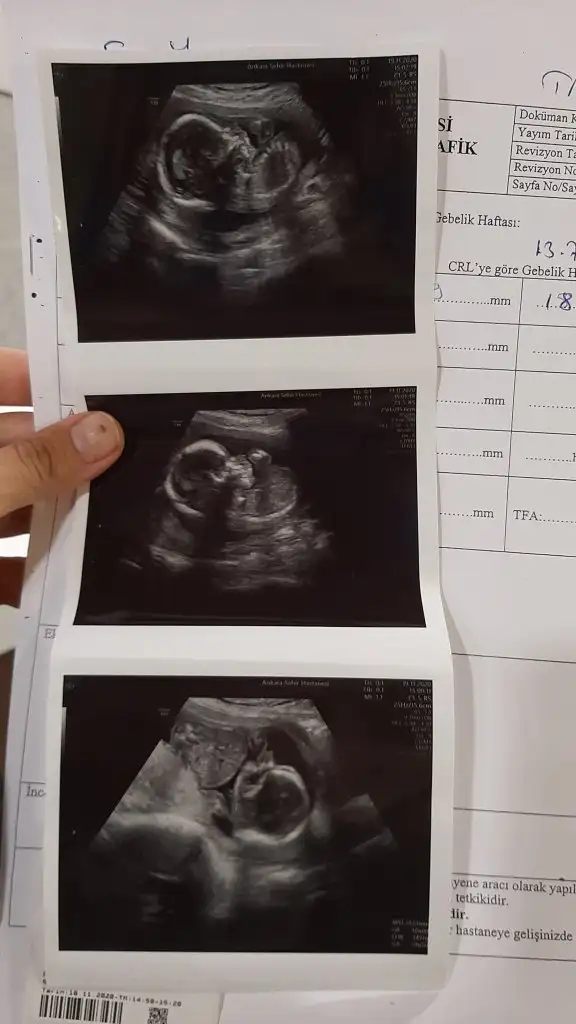

Kiz görünüyor başka USG varsa paylaşın 11 12 13 haftalar olmalıBenimkisinede bakar misiniz?Eki Görüntüle 2723115 Eki Görüntüle 2723116

Tsk. Ederim. Baska var ama 8. haftadaKiz görünüyor başka USG varsa paylaşın 11 12 13 haftalar olmalı